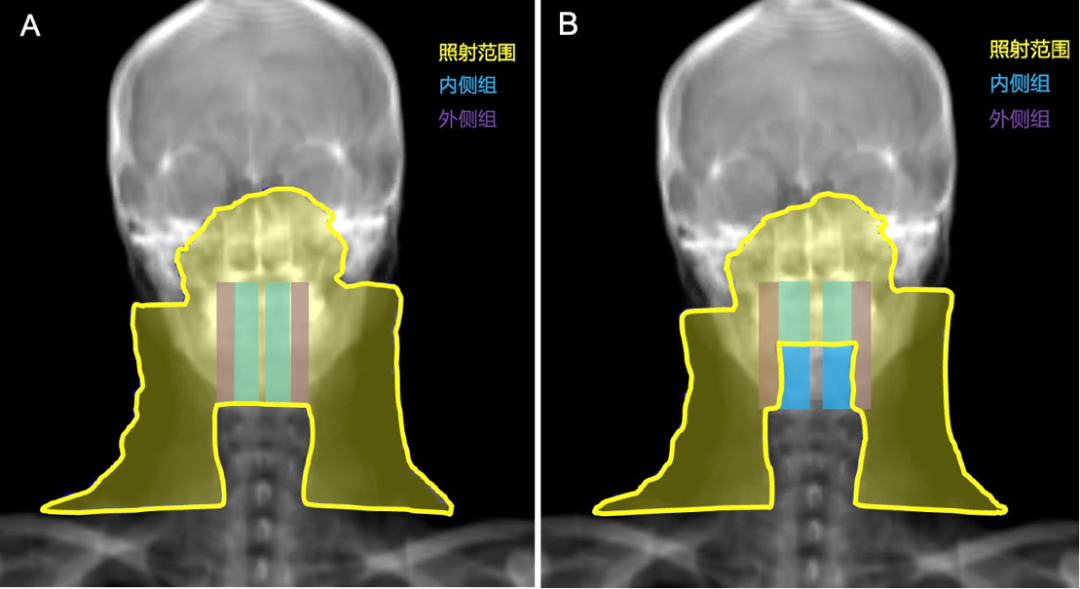

△鼻咽癌预防照射范围示意图

A对照组:内、外侧组咽后淋巴结区均接受预防照射(左)

B试验组:内侧组咽后淋巴结区豁免预防照射(右)